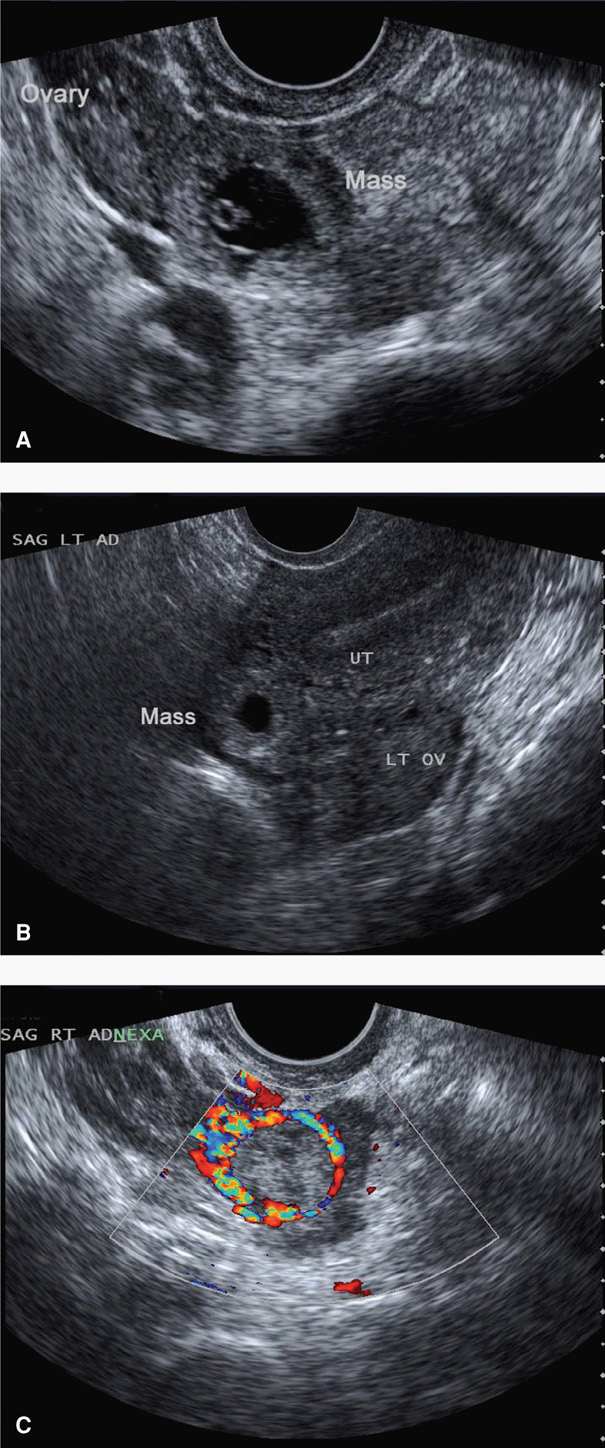

Ectopic Pregnancy Radiology Key

2 Common sonographic findings in ectopic pregnancies. (a) Empty uterine Thickened Endometrium Ectopic Pregnancy The mean initial endometrial stripe thickness of patients eventually diagnosed with an intrauterine pregnancy (13.42 ± 0.68 mm),. Different endometrial patterns have an important effect on the relationship between endometrial thickness (emt) and clinical. The mean endometrial thickness was thinner in patients with ectopic, compared with normal pregnancy (9.5 ± 5.7 mm vs 12.4 ± 5.9 mm; (1) an endometrial. Thickened Endometrium Ectopic Pregnancy.

Ectopic Pregnancy Undergraduate Diagnostic Imaging Fundamentals Thickened Endometrium Ectopic Pregnancy The mean endometrial thickness was thinner in patients with ectopic, compared with normal pregnancy (9.5 ± 5.7 mm vs 12.4 ± 5.9 mm; (1) an endometrial thickness < 8 mm coupled with a type c endometrium significantly increased the risk of ectopic pregnancy after. Different endometrial patterns have an important effect on the relationship between endometrial thickness (emt) and clinical.. Thickened Endometrium Ectopic Pregnancy.

Ectopic Pregnancy Undergraduate Diagnostic Imaging Fundamentals Thickened Endometrium Ectopic Pregnancy Different endometrial patterns have an important effect on the relationship between endometrial thickness (emt) and clinical. The mean initial endometrial stripe thickness of patients eventually diagnosed with an intrauterine pregnancy (13.42 ± 0.68 mm),. The mean endometrial thickness was thinner in patients with ectopic, compared with normal pregnancy (9.5 ± 5.7 mm vs 12.4 ± 5.9 mm; Compared with endometrial. Thickened Endometrium Ectopic Pregnancy.